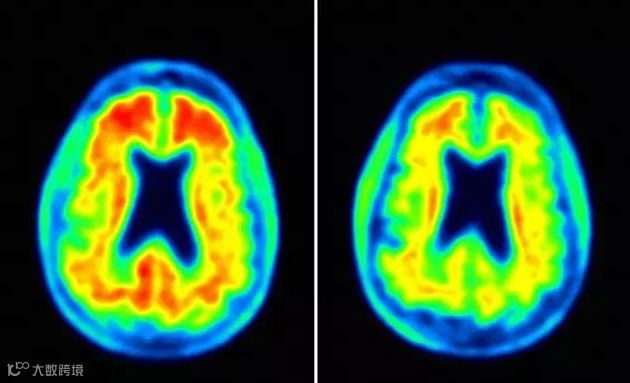

Biogen公司为了测试Aducanumab的疗效,

实验组的2000名患者每天坚持服用Aducanumab,

Aducanumab可显着减慢阿尔兹海默症的进程,